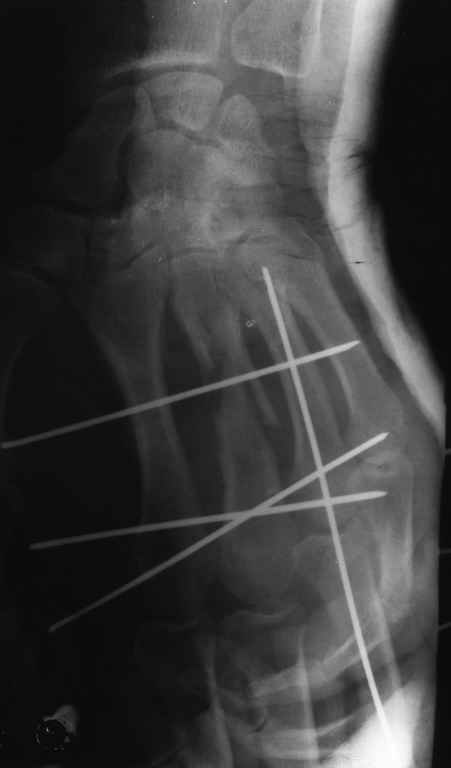

Диагноз: Стойкая Смешанная дермотеногенная контрактура 3,4 пальца правой кисти.

Судя по выписному эпикризу, рентгенограммам и фотографиям, пациенту

показано этапное лечение.